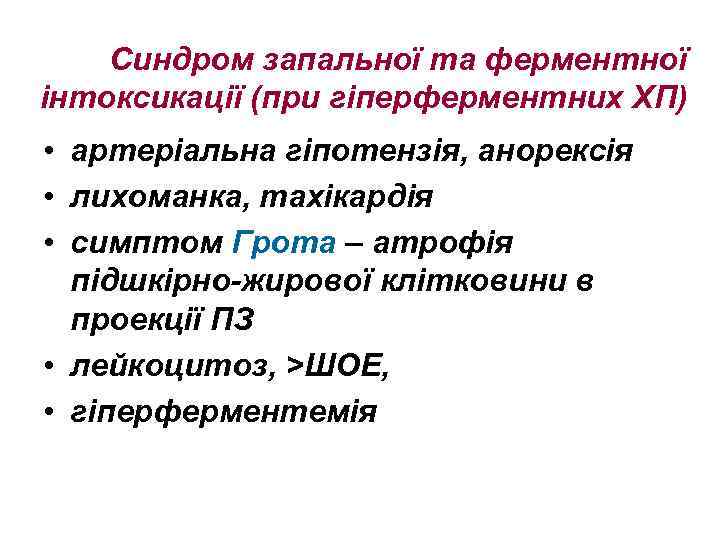

Синдром запальної та ферментної інтоксикації (при гіперферментних ХП) • артеріальна гіпотензія, анорексія • лихоманка, тахікардія • симптом Грота – атрофія підшкірно-жирової клітковини в проекції ПЗ • лейкоцитоз, >ШОЕ, • гіперферментемія

Синдром запальної та ферментної інтоксикації (при гіперферментних ХП) • артеріальна гіпотензія, анорексія • лихоманка, тахікардія • симптом Грота – атрофія підшкірно-жирової клітковини в проекції ПЗ • лейкоцитоз, >ШОЕ, • гіперферментемія